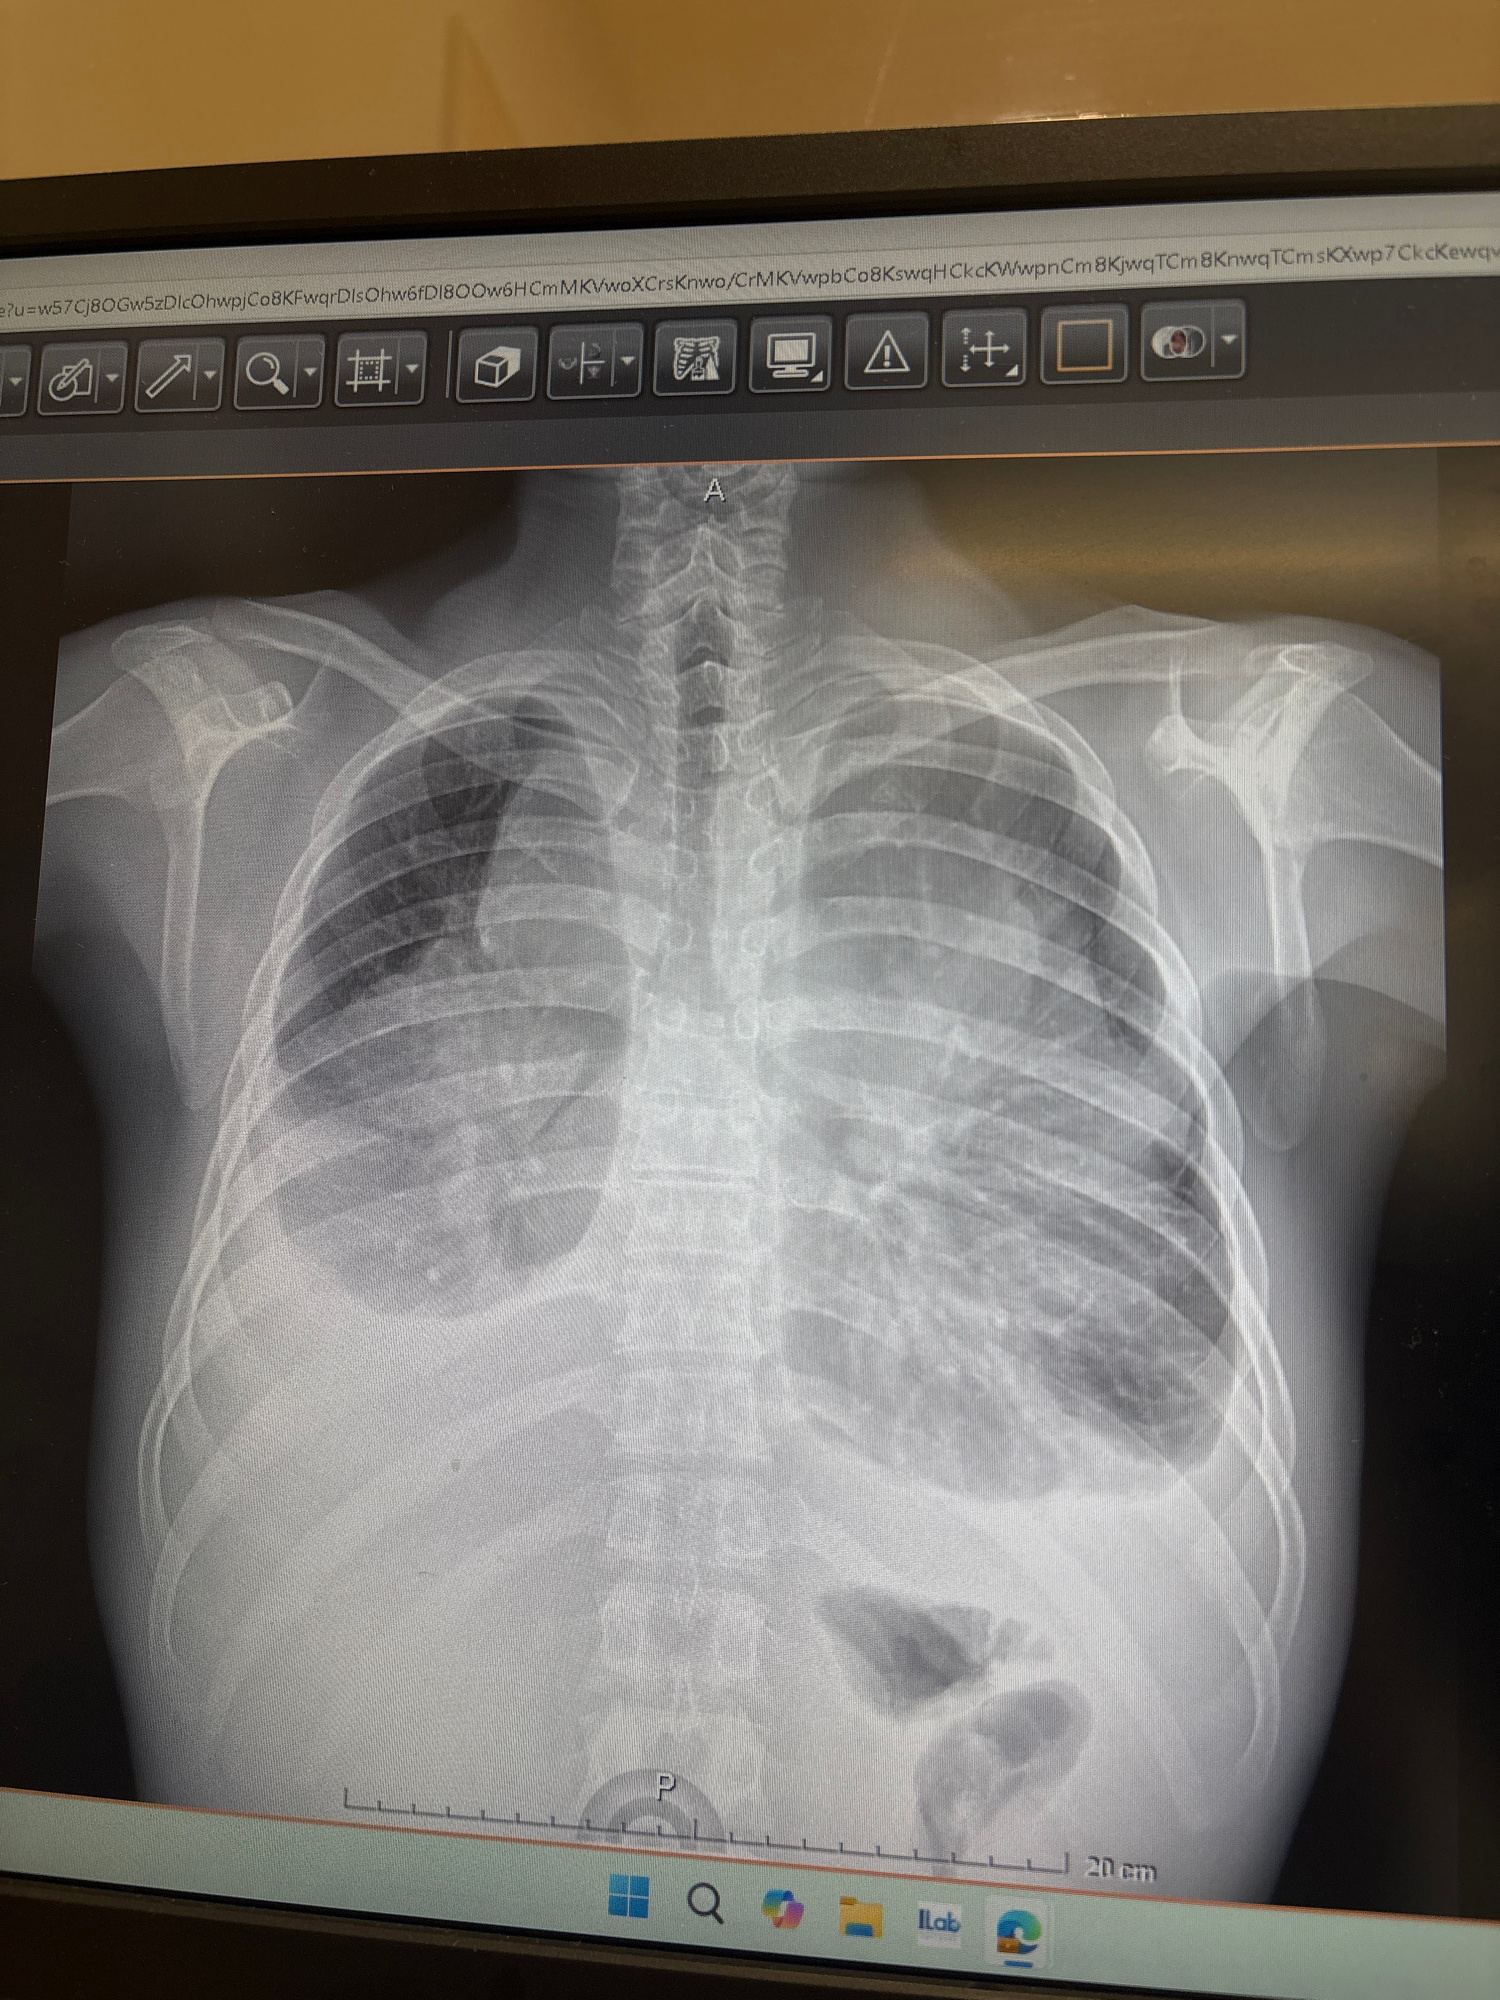

This image shows a frontal chest X-ray displayed on a digital screen. The ribs, spine, and shoulder bones are visible. The lung fields are darker in the middle compared to the edges, which is to be ex…read more